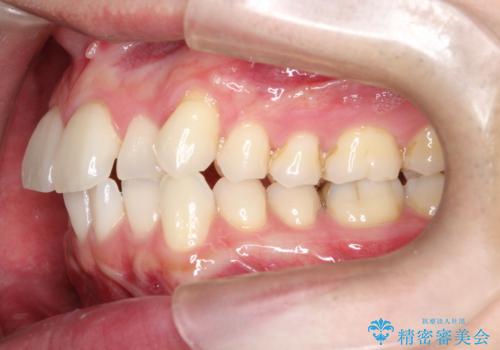

- 前歯の凸凹と顎の偏位を主訴に来院されました。

下顎の偏位を認めましたが、外科矯正を希望されなかったためできる範囲で顎の偏位を治すことができるよう治療を行なっております。

治療開始前に、下顎位の評価をおこなうことで、完成度の高い治療を行うことができました。